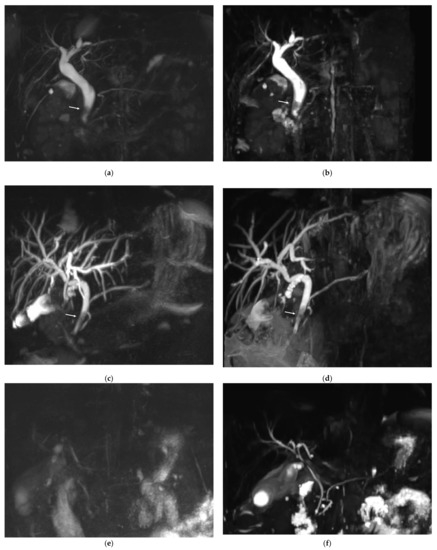

Figure 3 shows example MRCP images obtained with RT-MRCP and CS-BH-MRCP sequences with their qualitative image-quality criteria scorings.

Figure 3. Example of MRCP images obtained with RT-MRCP and CS-BH-MRCP sequences: (a,b) MRCP was performed in this 69-year-old female with chronic cholecystitis for suspected choledocholithiasis. The motion artefacts noted on the RT-MRCP sequence (a) were less noticeable on the CS-BH-MRCP sequence (b). Note that qualitative image-quality criteria were assessed on native images, whereas MIP images are shown on this figure. (a) For RT-MRCP, qualitative image-quality criteria were scored by senior radiologist, as follows: overall image quality: 3; presence of artefacts: 3; background suppression: 3; distal CBP visualization: 3; proximal CBD visualization: 4; cystic duct confluence: 3; right primary IHBD visualization: 3; left primary IHBD: 3; right anterior sectoral duct: 2; right posterior sectoral duct: 2; left medial duct: 2; left lateral duct: 3; distal and central MDP: 3; proximal MDP: 2. (b) For CS-BH-MRCP qualitative image-quality criteria were scored by senior radiologist as follows: overall image quality: 5; presence of artefacts: 4; background suppression: 4; distal CBP visualization: 4; proximal CBD visualization: 5; cystic duct confluence: 5; right primary IHBD visualization: 5; left primary IHBD: 5; right anterior sectoral duct: 5; right posterior sectoral duct: 5; left medial duct: 5; left lateral duct: 5; distal and central MDP: 5; proximal MDP: 4. RT-MRCP acquisition time was 5 min 5 s.